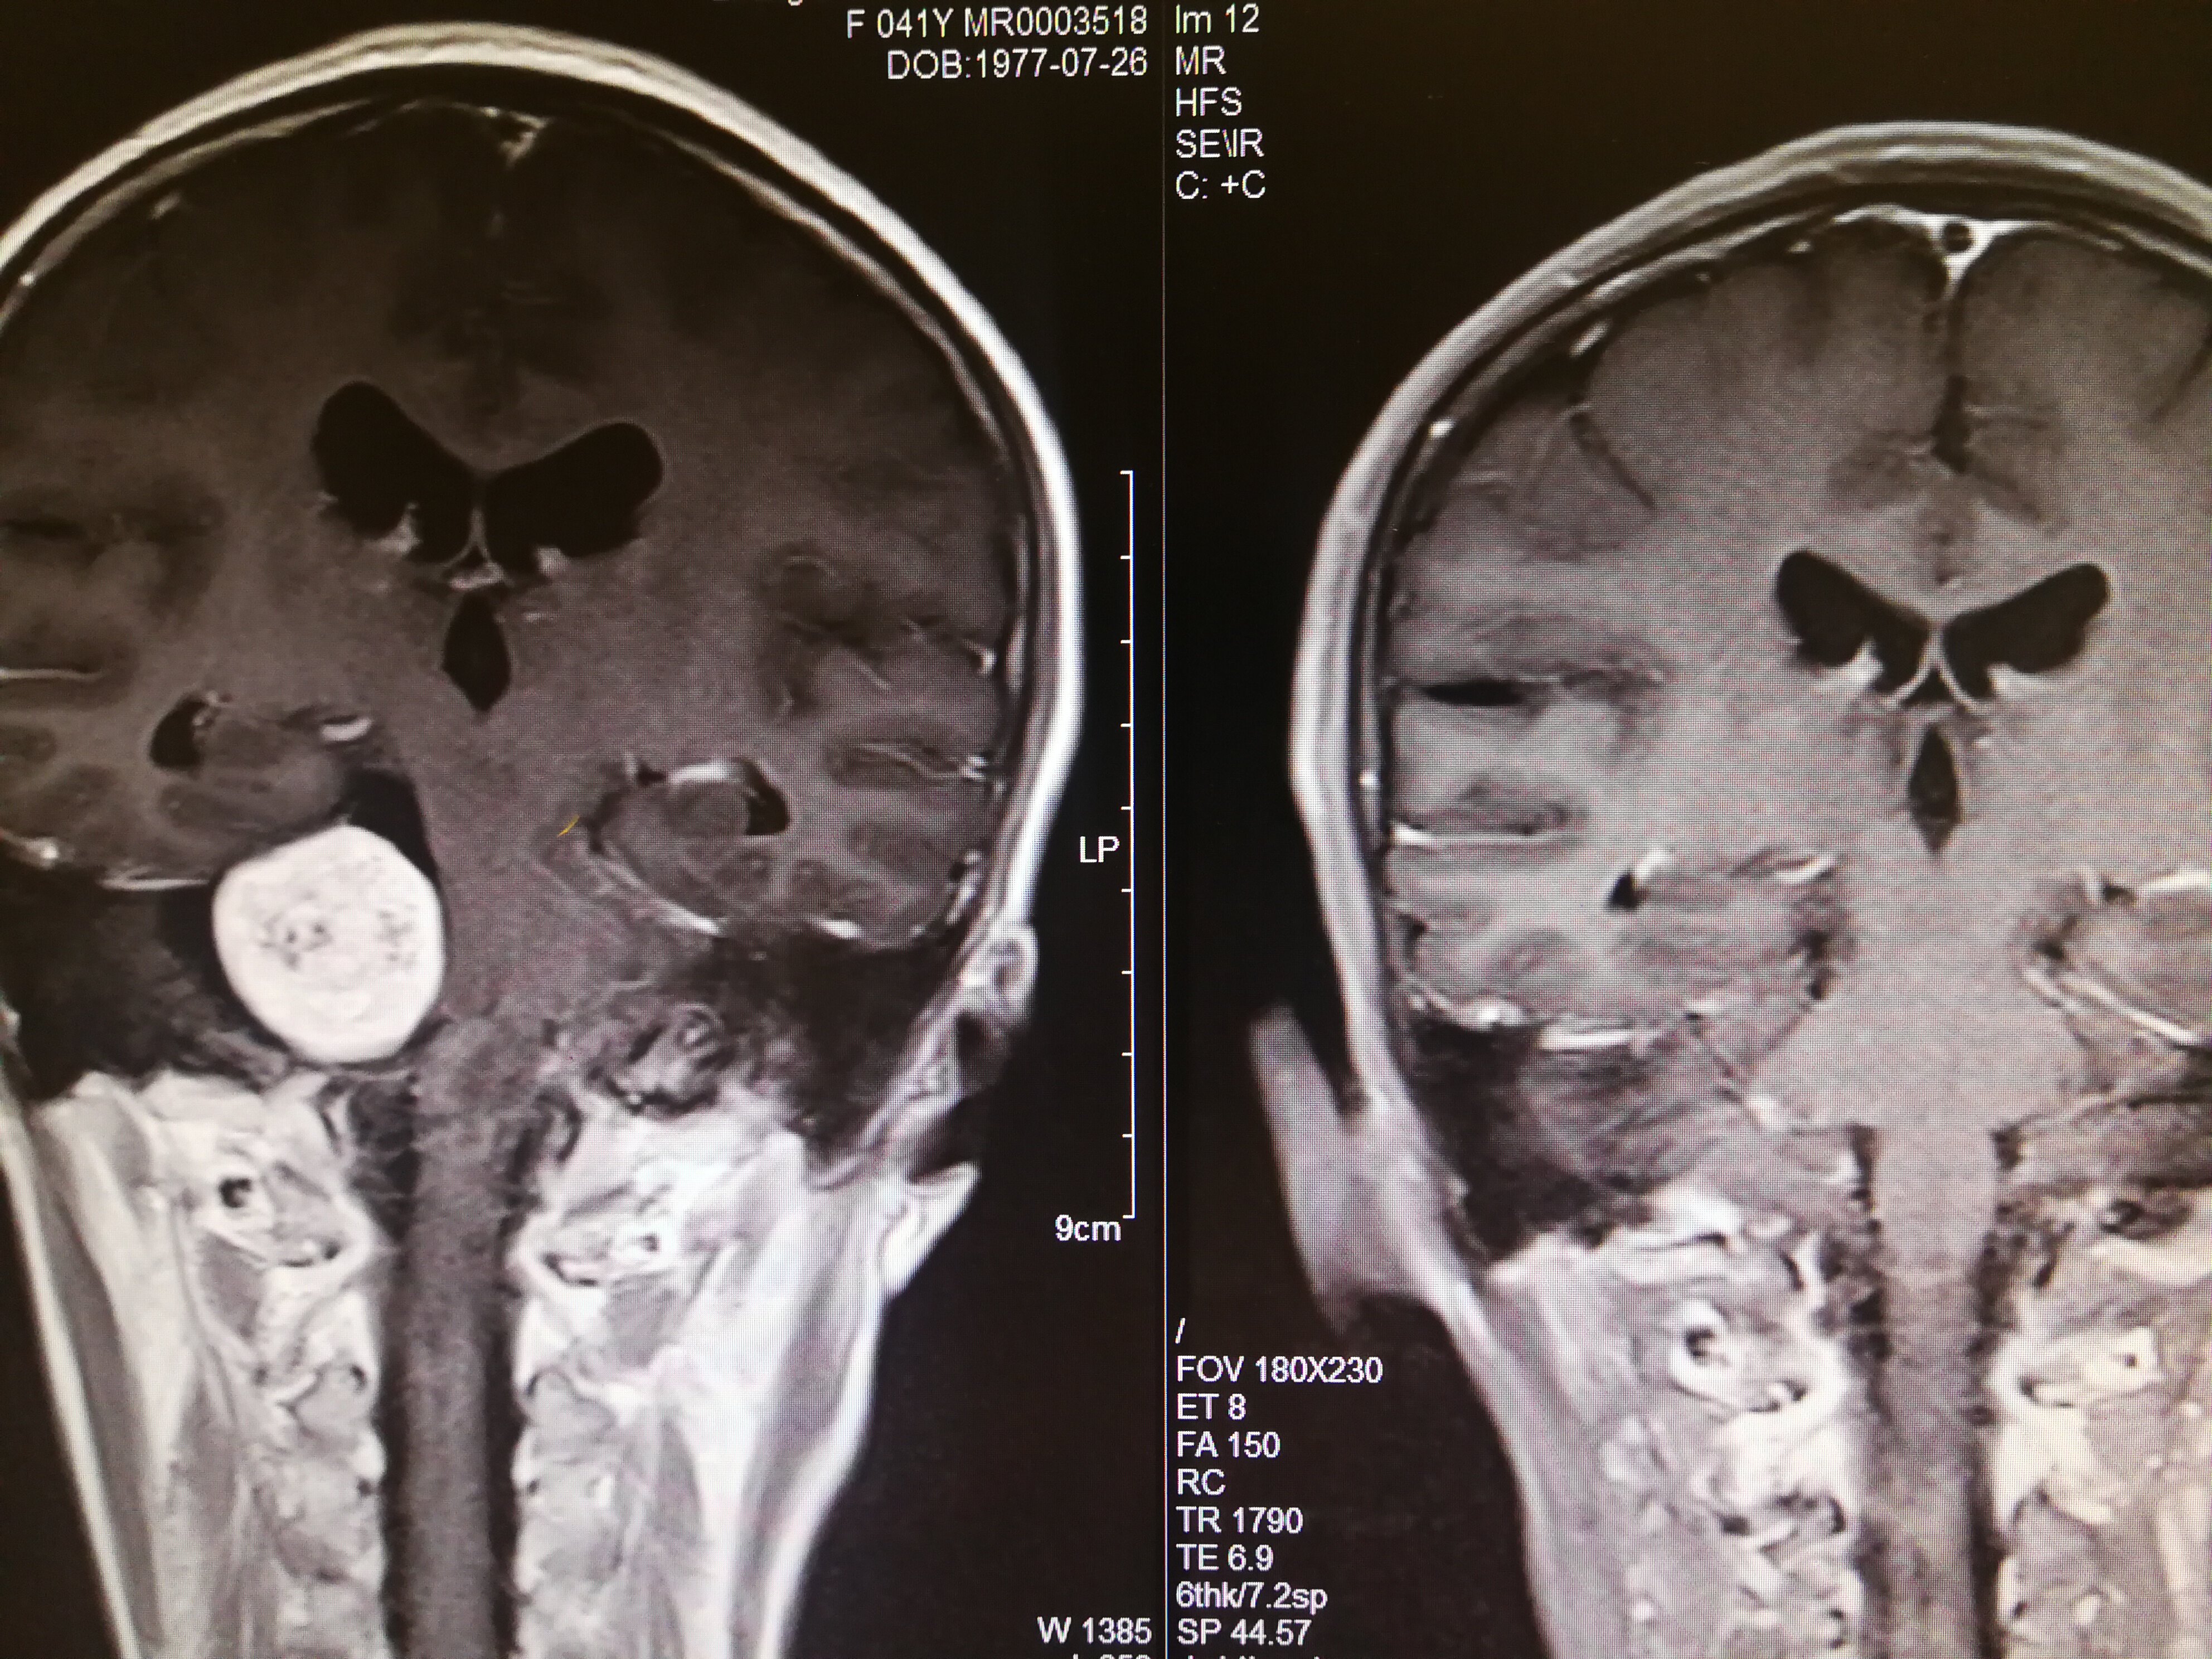

手术治疗听神经瘤是最主要的治疗方式,目前听神经瘤的手术已经非常成熟,只要没有明显的手术禁忌症首先应考虑手术治疗,并要求在电生理监测条件下完成手术,这样可以最大限度地保护面神经功能。以下是几例我们做的听神经鞘瘤手术前后核磁共振片子对照,除手术后听力不能恢复外,没有面瘫,脸部麻木,吞咽困难等颅神经症状,也无其他较明显的手术并发症发生。